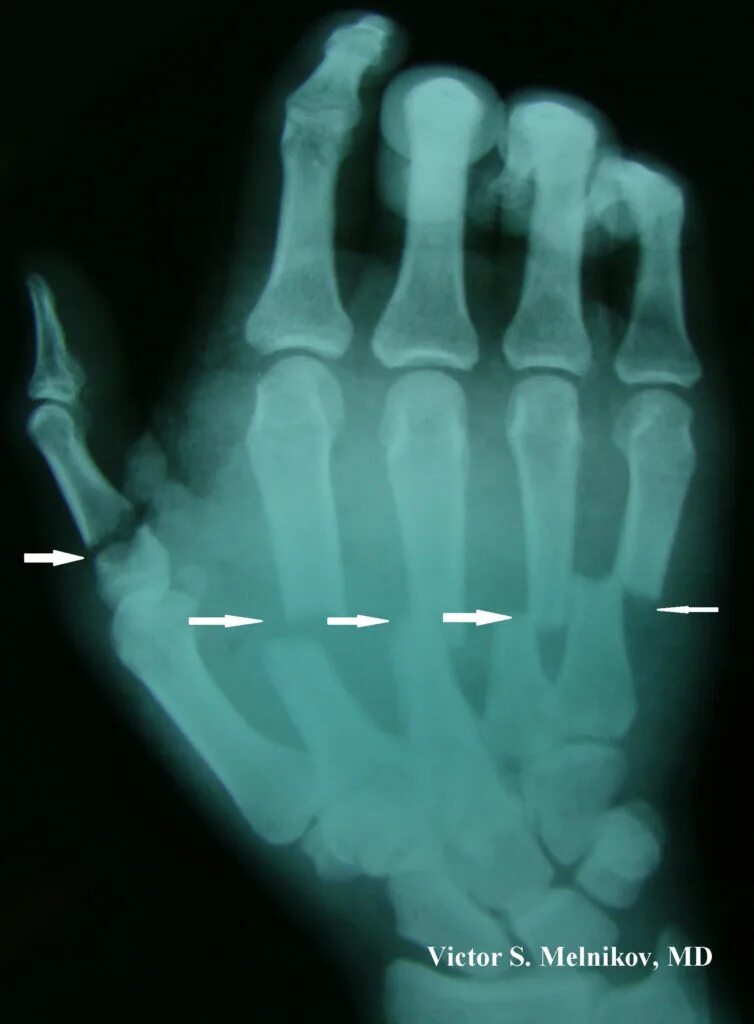

Перелом пятой пястной кости